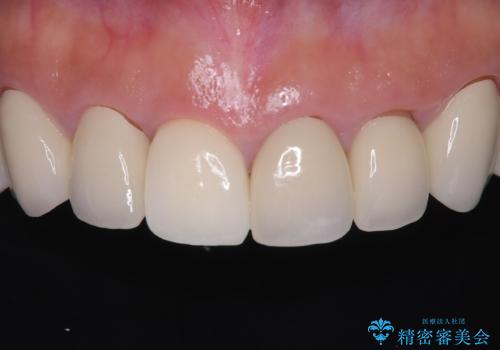

前歯の破折も1日で解決!抜歯即時インプラントで自然な笑顔へ

今回の治療では、まず原因となっていた前歯を慎重に抜歯し、その直後にインプラントを埋入しました。抜歯即時埋入は、歯を失うのとほぼ同時に新しい歯の土台を確保できるため、骨の吸収を防ぎ、仕上がりの美しさを保つ上で非常に有効です。また、治療当日に仮歯を装着することで、歯がない期間をなくし、患者様の精神的なご負担にも配慮しました。最終的に、周囲の歯と調和したオーダーメイドのセラミッククラウンを装着。機能性だけでなく、天然歯と見分けがつかないほどの自然で美しい前歯を取り戻していただけました。